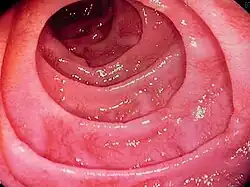

| Endoscopy of the duodenum showing fissured folds with a scalloped appearance | |

Most people with coeliac disease have a small intestine that appears to be normal on endoscopy before the biopsies are examined.[59] Endoscopic features of coeliac disease include scalloping of the small bowel folds (pictured), fissures, a mosaic pattern to the mucosa, prominence of the submucosa blood vessels, and a nodular pattern to the mucosa.[20]